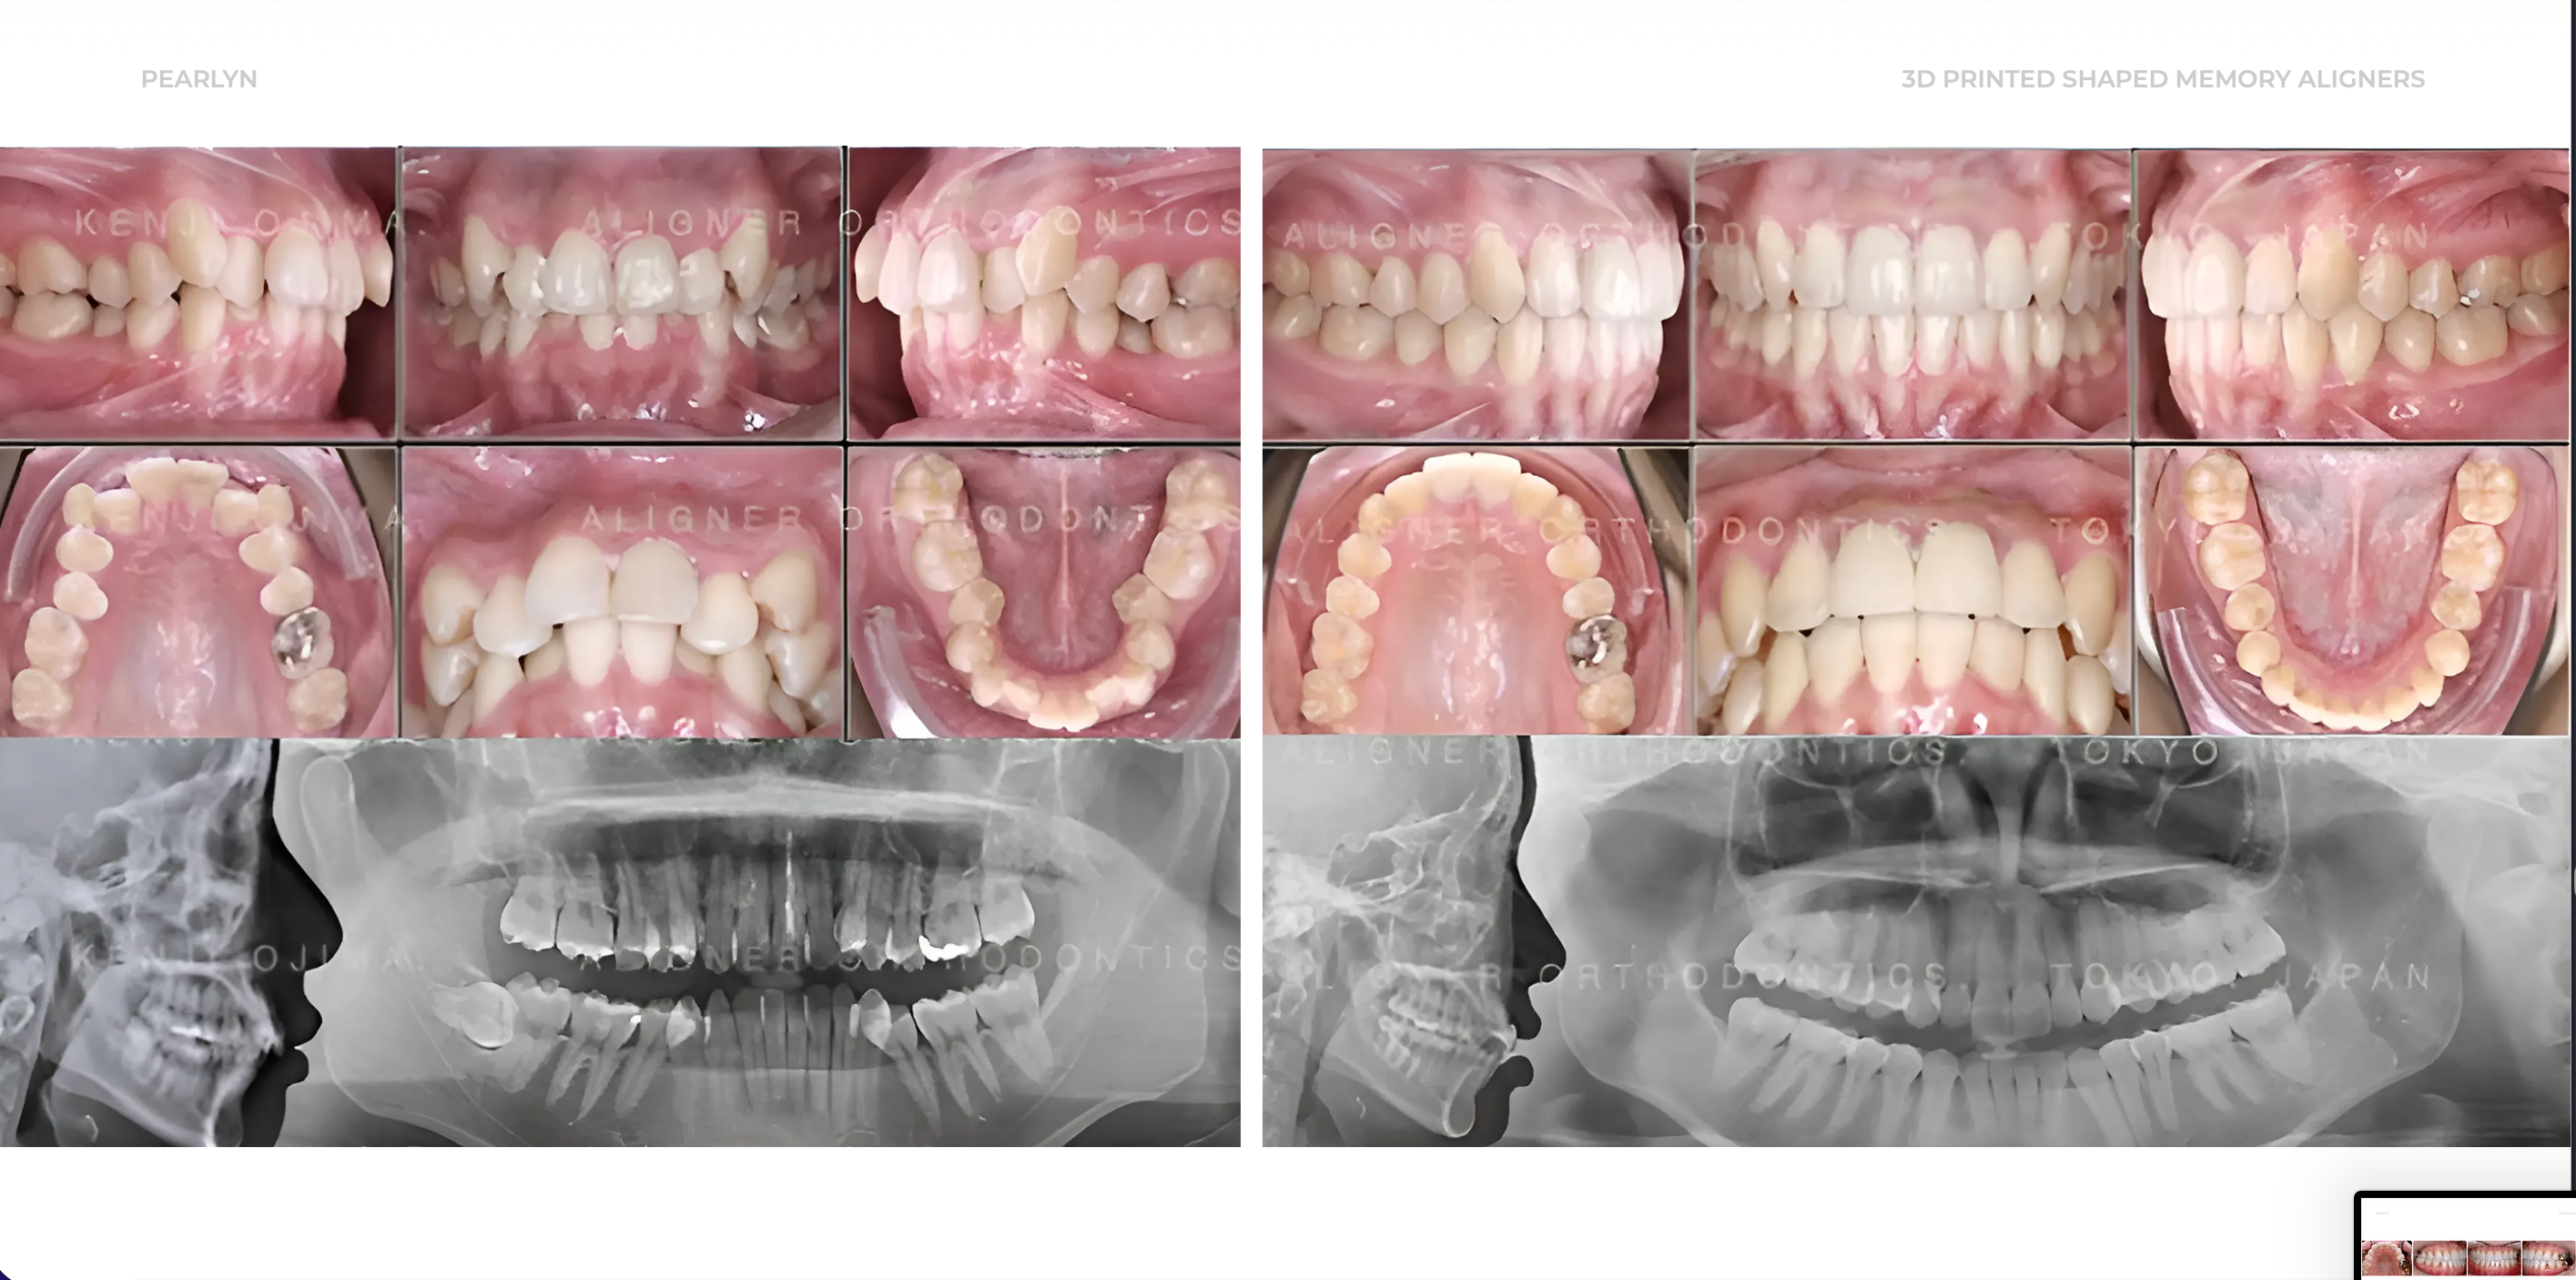

Pearlyn X Graphy

Official partner of Graphy the Global leader in 3D printing technology for shape memory aligners.